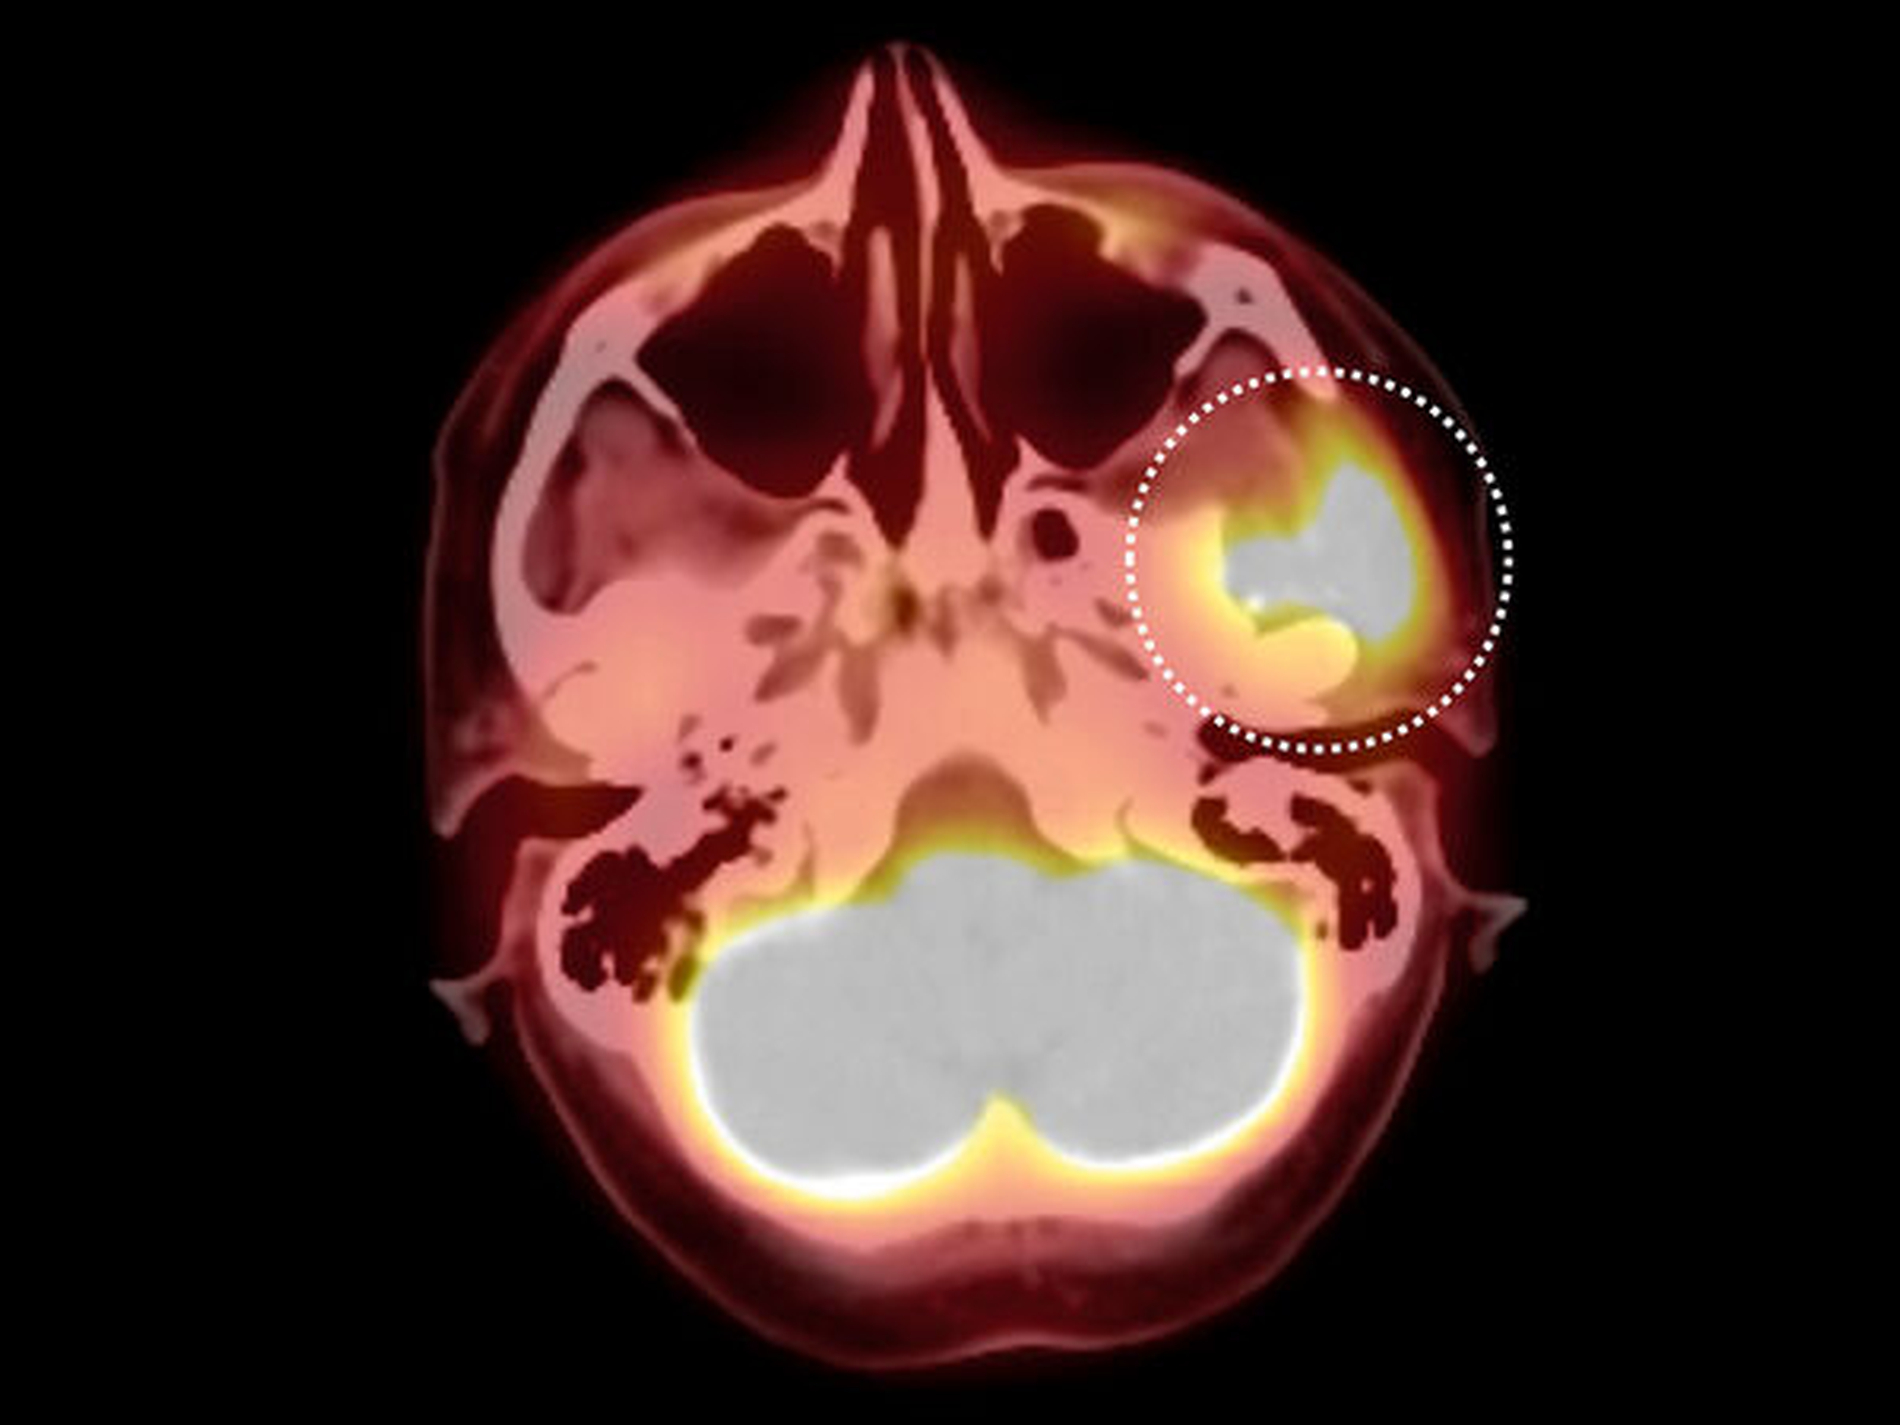

In der im Rahmen des komplettierenden Stagings durchgeführten 18-FDG- PET-/CT Untersuchung (Abbildung 2) zeigte sich eine massive Glukoseanreicherung im Bereich der linken Kiefergelenkspfanne. Anzeichen für eine Fernmetastasierung fanden sich nicht. Es erfolgte die CT-gesteuerte Punktion des Tumors an der Schädelbasis zur histologischen Einordnung. Die exakte histologische Klassifizierung des Tumors stellte sich als hochgradig diffizil heraus: Zunächst konnte nur ein wenig differenzierter, solide wachsender, maligner Tumor diagnostiziert werden. Ausgiebige Zusatzuntersuchungen und mehrere referenzpathologische Stellungnahmen konnten ebenfalls keine definitive histopathologische Einordnung des Befunds erzielen.